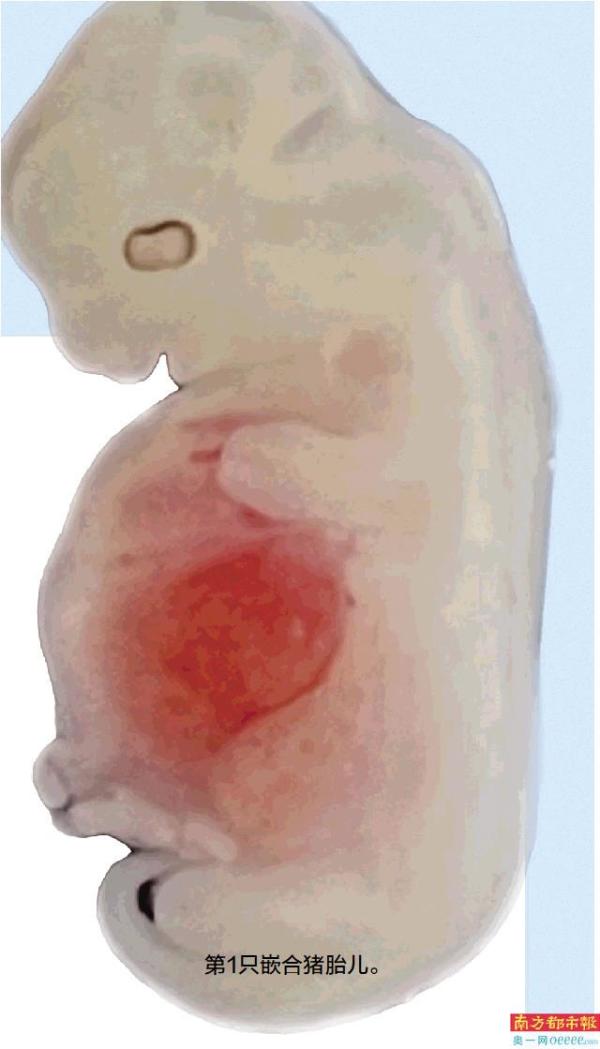

在猪胎儿中肾部位观测到一大团荧光 他们在猪体内成功培育人源中期肾脏

按照“3-4周胎龄内终止妊娠”的相关伦理规定以及国际惯例,这天,1头25天前移植了猪胚胎的代孕母猪要被终止妊娠,“这次给代孕母猪子宫做B超检测,看到胎儿存活情况特别好。”

DsRed荧光标记是为了便于直观地检测细胞,研究人员在人干细胞中定点敲入了表达DsRed荧光蛋白基因,从而让干细胞表达红色荧光。因此,当能从代孕猪胎儿的中肾部位观察荧光信号时,就说明表达红色荧光蛋白的人源细胞参与了肾脏的形成。

下午5点,代孕猪胎儿被送来实验室,攻关团队在做好一切准备后,将胎儿放在荧光显微镜下观测,当看到肾脏部位那里有一大团红色荧光,“好激动,起了鸡皮疙瘩。”

在随后大半年的时间里,不只是做25天的培育,还延长到28天的时候才终止妊娠。重复出现了红色荧光,这意味着,他们在猪体内成功培育出人源中期肾脏,人源化功能器官异种体内培育成功了。

最终,共获得2只胎龄25天、3只胎龄28天的中肾嵌合胎儿,这些胎儿的中肾内人源细胞占比最高可达70%,人源细胞参与形成的中肾小管所占比例最高可达58%。